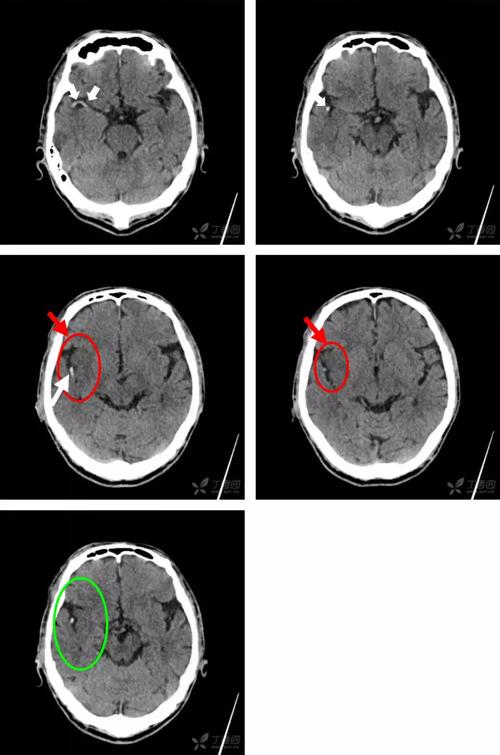

6 个病例学会「脑梗死」的 4 大 ct 征象

没有mri,超早期如何利用ct诊断脑梗死

掌握5个征象,ct也能诊断超早期脑梗死

超急性期大面积脑梗死 ct 平扫表现

脑梗死患者的头部ct,你真的会看吗?丨实战读片